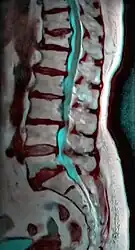

MRI of L5-S1 anterolisthesis -

Anterolisthesis L5/S1